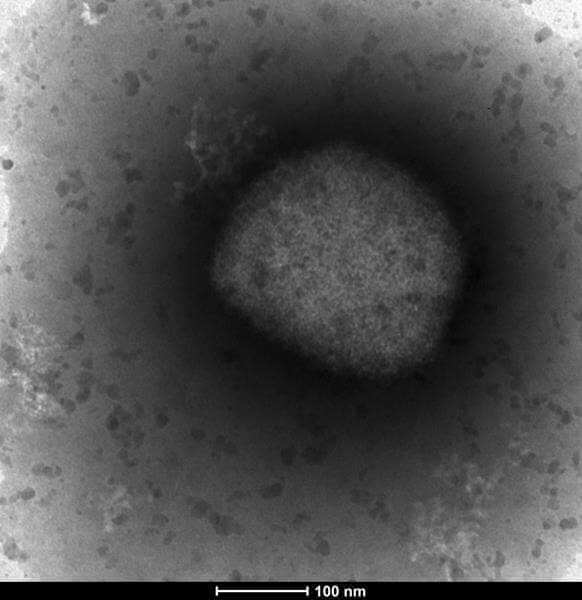

The BC Centre for Disease Control (BCCDC) has announced the first case of monkeypox in British Columbia, bringing the national total to almost 80 cases.